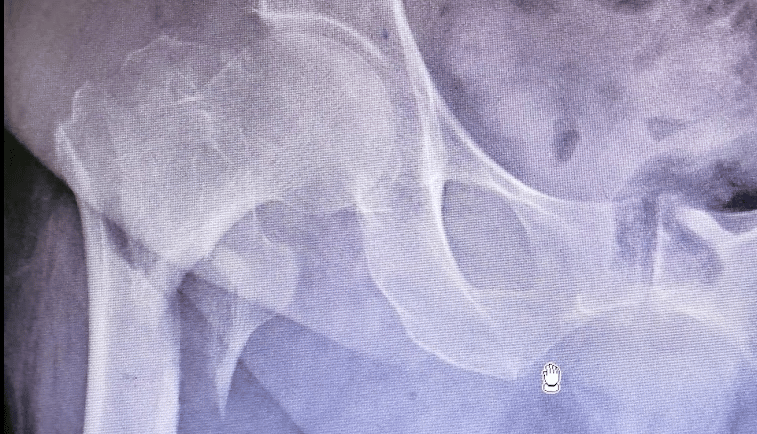

Diagnóstico

El diagnóstico se realiza mediante una evaluación clínica y estudios de imagen. El paciente suele presentar dolor intenso en la región de la cadera, incapacidad para caminar o cargar peso, y acortamiento o rotación externa de la pierna afectada. Las herramientas diagnósticas incluyen:

Radiografías: Permiten visualizar claramente la línea de fractura.